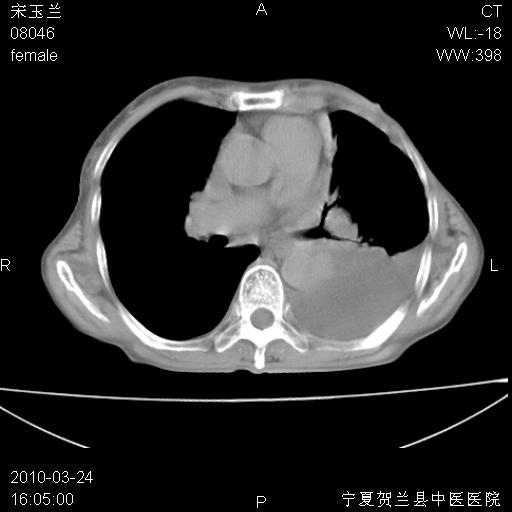

以下是引用zxl51642在2010-3-24 18:49:00的发言:[br]结合乳腺癌术后病史,考虑双肺及纵隔淋巴结多发转移、左侧胸膜转移并左侧大量胸水、左下肺膨胀不全。